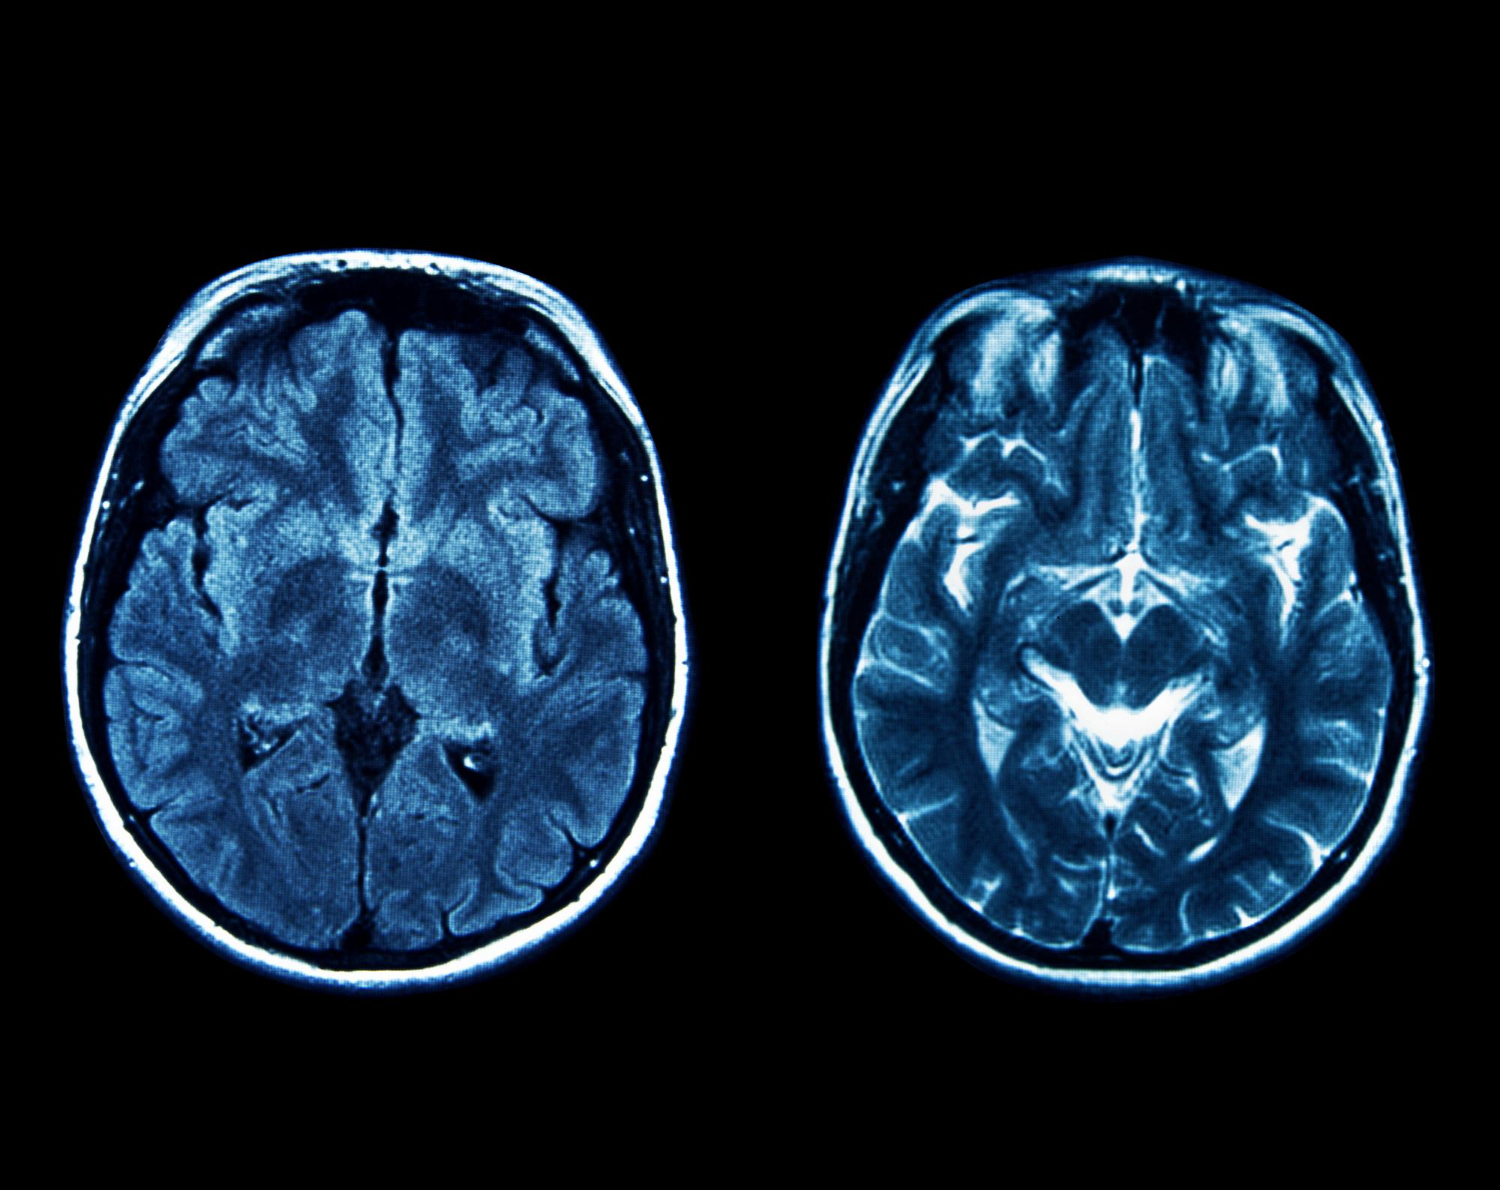

Que se passe-t-il dans notre cerveau lorsque nous mourons ? Cette question, posée depuis des siècles par les philosophes comme par les scientifiques, vient de recevoir un début de réponse. Grâce à une observation aussi imprévue que précieuse, l’équipe du Dr Ajmal Zemmar a réussi à enregistrer l’activité cérébrale d’un homme dans ses derniers instants. Pour la première fois, des données concrètes révèlent ce que pourrait vivre le cerveau humain juste après l’arrêt du cœur. Cette étude, publiée dans Frontiers in Aging Neuroscience, change notre compréhension de la mort, et ouvre de nombreuses pistes, aussi bien scientifiques qu’éthiques et philosophiques.

En 2016, un patient de 87 ans atteint d’épilepsie était surveillé en continu par électroencéphalogramme (EEG) dans un but médical. Pendant cette surveillance, il a subi une crise cardiaque fatale, permettant aux chercheurs d’enregistrer 900 secondes d’activité cérébrale autour de sa mort. Ce moment imprévu a offert une opportunité exceptionnelle : observer un cerveau humain en train de mourir en temps réel. Ce n’était pas prévu, mais cette coïncidence a ouvert une brèche unique dans le domaine des neurosciences.

L’analyse des données a révélé des signaux cérébraux complexes et coordonnés, même après l’arrêt cardiaque. Les chercheurs ont détecté cinq types d’ondes cérébrales : gamma, alpha, bêta, delta et thêta. Parmi elles, les ondes gamma, liées à la mémoire et à la conscience, ont retenu l’attention. Elles sont généralement associées à des fonctions cognitives élevées, comme la concentration, le rappel de souvenirs et la perception consciente. Le fait qu’elles persistent après la mort remet en cause ce que l’on pensait savoir sur la fin de la conscience.

Cette activité, notamment des ondes gamma enregistrées 30 secondes avant et après l’arrêt du cœur, suggère que le cerveau pourrait revivre certains souvenirs dans ses derniers instants. Dr Zemmar avance l’hypothèse que cela correspond à un « bilan de vie », un dernier effort du cerveau pour retracer des souvenirs significatifs. Une explication qui pourrait éclairer les témoignages de ceux qui ont vécu des expériences de mort imminente, où la vie défile en accéléré, accompagnée d’émotions intenses.

Cette étude marque un tournant. Elle offre un point de départ pour comprendre les derniers instants de la conscience humaine. Avec l’amélioration des outils de mesure comme l’EEG et l’imagerie cérébrale, les scientifiques pourront affiner leurs observations et tester leurs hypothèses. À terme, ces recherches pourraient changer nos pratiques médicales, nos lois, et notre vision de la vie et de la mort.